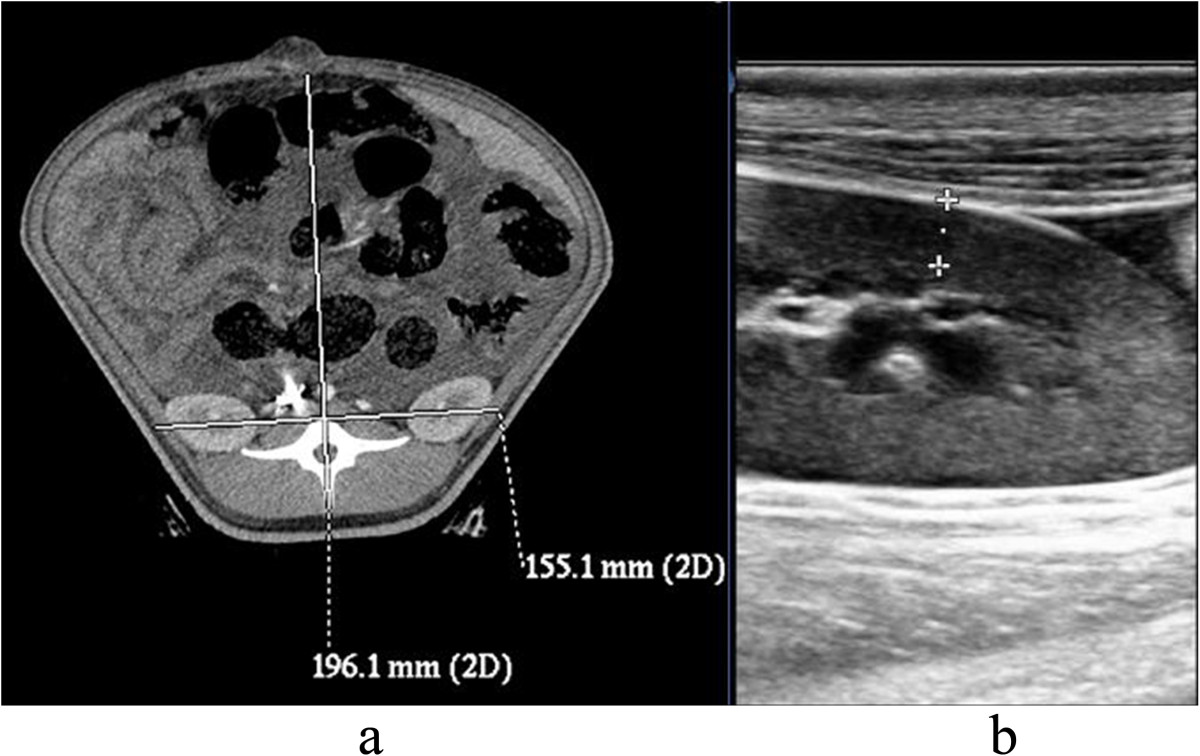

摘要:背景:探讨腹腔扩容(IAVI)对腹内高压(IAH)猪肾脏的影响。方法:八头猪均成功建立IAH模型,随机分为两组:IAVI组和假手术组。分别在休克前、IAH后2h 、手术后22h测量膀胱灌注压力、下腔静脉压、尿量。测定下列指标:血清肌酐、尿素氮、肾皮质厚度,腹部前后径/横径厚比,肾,肾窦的直径和肾组织湿/干比。结果:8头IAH小型猪模型的膀胱灌注压(IVP)为21.16±4.63毫米汞柱。腹部前后径/横径的比值显著增加。在IAVI组小型猪在观测期间存活,而2头假手术组猪在18 h和20 h时死亡。手术后22h,在IAVI组动物显示尿量(UV)增加、铬、Ur、VP和下腔静脉压显著降低降低。IAH后,肾皮质厚度、肾厚度明显增加。假手术组肾湿/干比高于IAVI组。结论:IAH后,IAVI帮助控制肾功能障碍、降低腹内压,从而减轻肾水肿、瘀血。关键词:腹内容积增大 腹内高压 创伤 休克 复苏背景:腹内压(IAP)超过12毫米汞柱被认为是病理性升高,称之为腹内高压(IAH)。由胰腺炎,外伤,毛细血管渗漏,临时腹腔填塞,内脏水肿导致的腹内压升高,可能会导致腹腔室隔综合征(ACS)。早期的研究表明,IAH可以提高肾静脉压力,增加肾实质的压力,并减少肾血流量和肾小球滤过率,导致少尿或无尿。肾缺血和肾实质受压可激活肾素-血管紧张素甾系统和随后引起水钠潴留。这一行动进一步增加血管阻力,并可能导致恶性循环。以往的研究表明,腹内压增加导致梗阻性和非梗阻性肾盂排泄受损。IAH的治疗包括手术和非手术的方式;然而,最佳的手术方案尚未确定。封闭式负压封闭引流术(VSD)是目前最常用的临时腹部封闭策略。腹腔扩容(IAVI)是一个已经修改了的治疗IAH技术;腹部手术对肾功能的影响的额外的研究是必要的,如成像研究比较手术前后的组织变化。本研究通过不完全阻断门静脉诱导IAH建立了一个大型动物的IAH模型并研究失血性休克及复苏后IAH对肾脏的影响及IAVI在提高临床治疗成功率的治疗效果。方法:动物:12头健康小型组,平均体重22.9±1.7公斤。失血性休克及复苏后IAH模型的建立:术前动物禁食12小时,手术前免费获得水,耳静脉注射氯胺酮(7.2毫克/小时/公斤)和3%戊巴比妥钠(6毫克/小时/公斤)麻醉动物。实验动物置于实验台上,皮肤消毒。插入气管,通过连有纯氧的呼吸麻醉机进行维持麻醉。分离右股动脉和静脉,插入单腔导管。通过一个三通管连接多功能传感器和监视器。右股动脉进行插管用于放血,而静脉插管用于下腔静脉输液和压力检测。开腹后,进行膀胱造瘘.. 分离门静脉和使用硬塑料管(外径为5毫米)和丝线结扎血管。撤除硬塑料管,创建门静脉完全阻塞模型模拟严重肝损伤的治疗肝周填塞过程。股动脉放血至平均动脉压(MAP)达到50毫米汞柱,血液储存在血袋。腹壁切口采用分层缝合闭合。休克后一个小时,所有丢失的血液,连同Ringer溶液(血液的两倍),被输送回体内。Ringer溶液连续给药,直至复苏。当IAP≥12毫米汞柱IAP并维持1 h被认为IAH模型成功建立。成功地建立了模型,但4只动物死于失血性休克。动物分组与相位观测:四头死亡动物被排除在研究之外。用抛硬币的方法,剩余的8个动物分为IAVI组(n = 4)和假手术组(n = 4)。IAVI治疗程序进行如下:除去腹部切口缝合,延长切口从剑突至耻骨联合、松动和去除门静脉结扎,去除肠上肠网膜。聚乙烯醇明胶海绵约30×20厘米放在大网膜,缝合至腹壁层。从切口一侧抽取引流管嵌入海绵内。采用透气性好、透气性好的生物渗透膜覆盖切口和海绵,直至切口封闭。通过连续抽吸引流管被用来维持60毫米汞柱到80毫米汞柱的负压,直到动物被剖杀。在假手术组,剪开腹部切口缝合,切口从剑突至耻骨联合处,松开并拆下的门静脉结扎物和分层缝合直接关闭切口。休克前, IAH后2 h和术后22 h开始测量。静脉注射0.2克氯胺酮和10毫升的10%氯化钾处死动物。肾功能指标测定:每小时获取尿量(UV)测量。休克前, IAH后2h,术后22h下腔静脉导管获得的血液样本进行测定肌酐和尿素氮水平。影响肾功能指标的测量:休克前, IAH后2 h,术后22 h和26 h测量以下指标:(1)膀胱灌注压(IVP):在膀胱排空,50毫升的生理盐水注入膀胱,硅胶管竖立。当下降到一个平稳水平时,耻骨联合上方的水柱垂直高度为膀胱灌注压力。(2)下腔静脉压(CVP):使用多功能监护仪通过下腔静脉导管测定下腔静脉压。(3)彩色多普勒:根据右肾获得的数据,通过测量肾皮质厚度,观察肾盂和肾盏是否存在分离。(4)增强CT扫描:测量腹部的前后径与横径的比值(在左肾静脉水平,皮下脂肪被移除)。根据右肾获得的数据,测量肾脏最宽横切面的肾厚度和肾盂长度。(5)肾组织的湿/干比:取左肾组织的上部1/8,取肾标本称重,放置在60°C的干燥炉内放置3天。湿/干比4-4.5或更高的显示有严重的脏器水肿。6)肾组织病理学:取右肾上部1 / 8,固定在10%福尔马林,石蜡包埋,切片,进行HE染色,光镜下观察。结果:IAH模型:平均体重为22.90±1.70公斤和MAP基线值为118±14.30毫米汞柱。放血直到MAP达到50毫米汞柱;放血量为648±98毫升。IVP基线6.65±0.50毫米汞柱。当IVP达到21.16±?4.63 mmHg持续3.20±0.60 h,所需的Ranger液量为76±3毫升/公斤/小时。两头猪出现直肠脱垂和压力性尿失禁。12头猪中8头成功建立IAH模型(66%)。在IAVI组,四猪存活到观察期间。在假手术组, 4头猪中的2头,分别在IAH开始后18 h和20 h,由于呼吸衰竭死亡。IAH开始后2h UV明显小于休克前(分别是55±11 ml/h vs. 156±35 ml/h, P<0.01)。在IAVI组,尿量恢复正常(120±23毫升/小时和55±11 ml/h,p<0.01)但未达到正常水平。假手术组尿量明显低于相比IAVI组。IAH开始后2 h,血Cr和UR值增加,无显著性差异。IAVI治疗后,CR和UR继续缓慢增加,在假手术组,CR和Ur显着高于其他组中的值。在假手术组肾组织湿/干重比值显著高于IAVI组。影响肾功能的相关因素:IAH后两小时,静脉肾盂造影,下腔静脉压明显高于休克前。IAVI治疗22后,IVP和下腔静脉压显示显著降低,均略高于休克前,但无显著性差异。假手术组下腔静脉压和IVP显著高于IAVI组。影像学改变:计算了前后径与横径的比值,IAH开始后2h比值显著高于基线值。CT检测右肾肾的高度,表明IAVI组和假手术组之间无显著性差异。B超测定右肾皮质厚度,这表明IAVI治疗组和假手术组之间无显著性差异。用CT测量右肾窦直径。IAH无明显变化。所有动物的任何相位点,没有肾盂积水或肾盂和肾盏的分离。病理结果:假手术组肾组织可见明显的血瘀,炎症细胞浸润。在IAVI组、轻度瘀血或无瘀血和炎症细胞轻度浸润。结论:腹腔室隔综合征常发生于危重病人,可能会影响各器官系统,肾脏是最常受影响的器官。观察IAVI诱导的IAP减少和肾功能改善之间的相关性。IAVI帮助控制IAH后肾功能障碍,可降低腹内压,从而减轻肾水肿、瘀血。